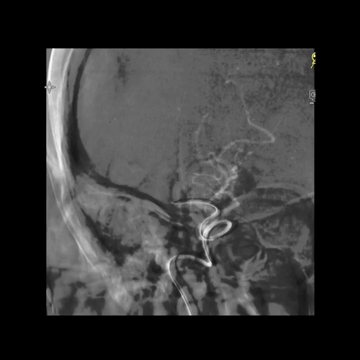

5F中间管负压下退至颈内动脉末端时,经长鞘造影示右侧MCA再通。

持续负压下回收中间管,后造影示颈内动脉后交通位置闭塞,提示血栓较大且坚硬,从5F中间管头端脱落。

血栓坚硬,微导丝最终成袢通过闭塞位置,微导管跟进进入M1,释放支架。

抽拉结合取栓后造影:颈内动脉远端和M1多发充盈缺损;更换6F中间管,且6F长鞘上高到C1远端。

微导丝微导管超选到M1下干。

微导管造影证实真腔,再次送入和释放支架。

抽拉结合取栓后造影示:闭塞完全再通,取出数块大血栓。